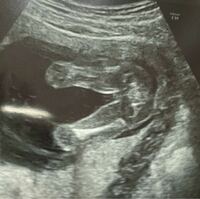

今日の検診で今のところは女の子かな と言われたんですが姉にエコ Yahoo 知恵袋